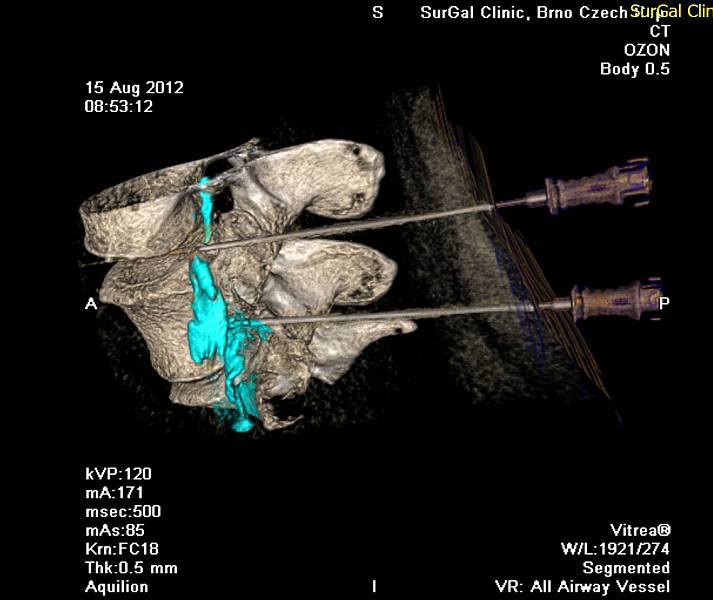

Zákrok se provádí pod navigací CT přístrojem za sterilních podmínek.

- Pacient leží na břiše. Po základním vyšetření na CT a přípravě operačního pole lékař provede lokální anestezii kůže a podkoží a zavede tenkou atraumatickou spinální jehlu přesně k postiženému úseku páteře do epidurálního prostoru. Optimální cestu a umístění hrotu jehly určí lékař, cílová oblast je velmi malá a je tak pravděpodobné, že ověřování na CT bude opakované. Po ověření správné pozice jehly lékař aplikuje směs buď kyslíku a ozonu nebo anestetika, steroidního protizánětlivého léčiva a kontrastní látky, a provede se ověření distribuce léčiva.

2. Muž, 41 let. Na MR objemná hernie L4/5 velikosti 11mm téměř vyplňující páteřní kanál, útlak nervových kořenů. Opakovaně doporučována operace, kterou pacient odmítl. Jako alternativu zvolil ozonoterapii s aplikací ozonu do disku L4/5 a periradikulárně. Byly aplikovány celkem 3 dávky ozonu. Viz obr.7a

Na kontrolním MR po 6 měsících je patrná výrazná redukce velikosti hernie, vymizely fragmenty, uvolnil se páteřní kanál a do značné míry i nervové kořeny. Subjektivně výrazná úleva téměř k normálu. Viz obr. 7b